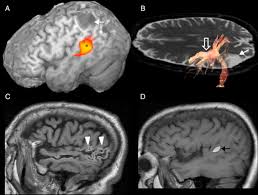

Estimulacion Magnetica En Afasia Clinica San Vicente De Dano Cerebral

Estimulacion Magnetica En Afasia Clinica San Vicente De Dano Cerebral from www.clinicasanvicente.es